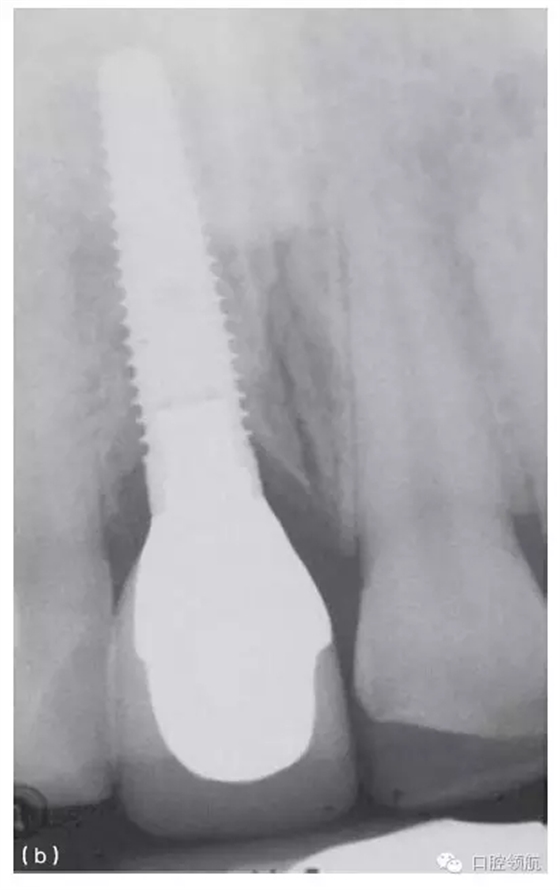

種植體植入時(shí)如果太偏舌側(cè),會(huì)造成冠修復(fù)時(shí),唇側(cè)頸部凸度異常(圖10.1b,圖10.27),或是冠的瓷層必須蓋過頰側(cè)軟組織以形成理想的頸部外形(圖10.28a~c)。這種覆蓋會(huì)使口腔衛(wèi)生的維護(hù)更困難,同時(shí)也會(huì)由于軟組織的根向退縮產(chǎn)生美學(xué)問題。在有的情況下,采用冠覆蓋頰側(cè)軟組織(圖10.29a~c)的設(shè)計(jì)也是必需的(類似于某些固定局部義齒的橋體),否則,冠將呈現(xiàn)出明顯的頸部缺損或外形凸度不足的情況(圖10.30a,b和圖31a,b)。

當(dāng)種植體植入的位置,是鄰牙唇舌向中點(diǎn)偏舌側(cè)時(shí),修復(fù)時(shí)就必須采用冠來覆蓋唇側(cè)的軟組織(類似于某些局部固定義齒的橋體),以獲得正常的頸部外形。另外,可采用水平埋入式的卵圓形(類似于卵圓形橋體)來支持軟組織以獲得更美觀的外形(圖10.32a~d)。

在種植體和最終修復(fù)體之間,應(yīng)考慮設(shè)計(jì)適合的穿齦輪廓和過渡外形,以使其從齦溝中穿出時(shí),顯得很自然。當(dāng)修復(fù)體穿出齦溝時(shí),為了從圓直徑的種植體過渡到天然牙的外形,在組織高度不足時(shí),需要使用個(gè)性化角度基臺(tái),或增加齦下過渡的角度。盡管有這些方法,但要想獲得預(yù)期的效果,有時(shí)也必須采用外科手術(shù)的方法來矯正(圖10.24b~e)。